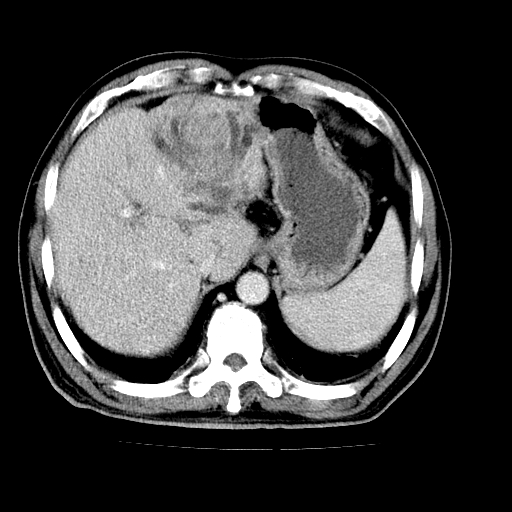

男,66岁,上腹部不适、黄染一周。彩超示:肝左叶占位,肝内胆管扩张,胆总管扩张,胆总管占位?

肝左叶不规则软组织肿块影,边缘不规整邻近肝实质受累分界不清;肝内胆管(左叶)明显扩张成“软藤状”,诊断:肝左叶胆管细胞癌。

肝左叶占位性病变,并胆管扩张,符合胆管细胞癌ct表现,门脉左支受累,左肾囊肿。窗宽太窄了,其他的看不清

肝左叶不规则软组织肿块影,边缘不规整邻近肝实质受累分界不清;肝内胆管(左叶)明显扩张成“软藤状”,诊断:肝左叶胆管细胞癌。胆囊钙乳症。

胆囊缩小,其内胆汁浓缩,也提示梗阻部位应该位于胆囊管起始部以上或是胆囊管受累及,支持肝外胆管癌。